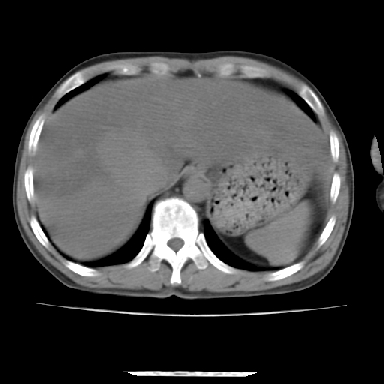

标题: CT7372:脂肪肝?外伤? [打印本页]

标题: CT7372:脂肪肝?外伤?

m 45 车祸,硬膜下血肿

窗宽太宽,调低点就好了,应该是不均质脂肪肝表现,请结合临床,单纯肝挫伤  其内无出血灶很少见,必要时做mri检查

窗宽太大,对比度太差了。局限性脂肪肝也有可能,但是亦不排除外伤性改变,增强扫描应该也还可以鉴别的。

肝内未见出血灶,但不能除外外伤性肝损伤,所示层面应考虑弥漫性脂肪肝.请结合临床必要时做mir检查

肋骨无骨折,腹腔未见游离液体,所以不均匀脂肪肝首先考虑,但如果病人情况允许还是做个增强检查放心

考虑不均匀性脂肪肝,肝包膜下光整,肋骨无异常,无腹水征,不支持肝挫伤。